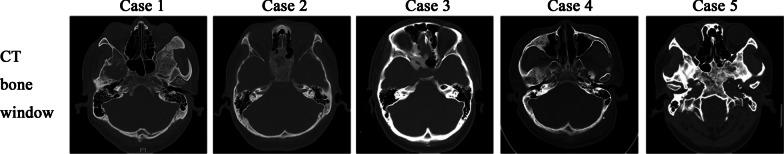

The cohort comprised four men and one woman (median age, 39 years). The symptoms mainly included headache, dizziness, fatigue, polyuria/polydipsia, hypogonadism, and blurred vision. CFD most commonly involved the sphenoid bone (n = 4). Four patients underwent surgery to remove the CP (one trans-sphenoidal and three transcranial resections); complete and subtotal resection were achieved in two patients, respectively. The tumor subtype was adamantinomatous in three patients and unknown in one. The common postoperative complications were panhypopituitarism, diabetes insipidus, and hypothyroidism. The mean follow-up duration was 57.2 months. Two patients required postoperative hormone replacement therapy. Three patients underwent genetic study of the tumor specimens; GNAS mutations were not detected, but these patients were positive for Gsα protein.

该队列包括 4 例男性和 1 例女性(中位年龄,39 岁)。症状主要包括头痛、头晕、乏力、多尿/多饮、性腺功能减退和视力模糊。CFD 最常累及蝶骨(n = 4)。4 例患者接受手术切除 CP(1 例经蝶窦入路,3 例开颅手术);2 例患者分别达到全切和次全切除。肿瘤亚型 3 例为造釉细胞瘤型,1 例为未分类。常见的术后并发症包括全垂体功能减退、尿崩症和甲状腺功能减退。中位随访时间为 57.2 个月。2 例患者术后需要激素替代治疗。3 例患者对肿瘤标本进行了遗传研究;未发现 GNAS 突变,但这些患者的 Gsα 蛋白阳性。